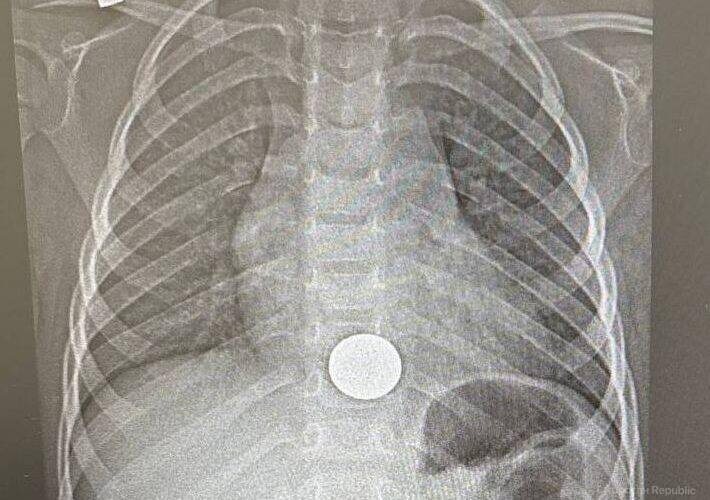

ΠœΠ°Π»ΡŒΡ‡ΠΈΠΊ поступил Π² Π±ΠΎΠ»ΡŒΠ½ΠΈΡ†Ρƒ с ΠΆΠ°Π»ΠΎΠ±Π°ΠΌΠΈ Π½Π° Π±ΠΎΠ»ΠΈ Π·Π° Π³Ρ€ΡƒΠ΄ΠΈΠ½ΠΎΠΉ. Π’Ρ‹ΡΡΠ½ΠΈΠ»ΠΎΡΡŒ, Ρ‡Ρ‚ΠΎ ΠΎΠ½ случайно ΠΏΡ€ΠΎΠ³Π»ΠΎΡ‚ΠΈΠ» ΠΌΠΎΠ½Π΅Ρ‚Ρƒ.

Π’ ΠΈΡ‚ΠΎΠ³Π΅ Ρ…ΠΈΡ€ΡƒΡ€Π³ эндоскопичСски ΡƒΠ΄Π°Π»ΠΈΠ» ΠΈΠ½ΠΎΡ€ΠΎΠ΄Π½ΠΎΠ΅ Ρ‚Π΅Π»ΠΎ. Π Π΅Π±Π΅Π½ΠΊΠ° ΡƒΠΆΠ΅ выписали.